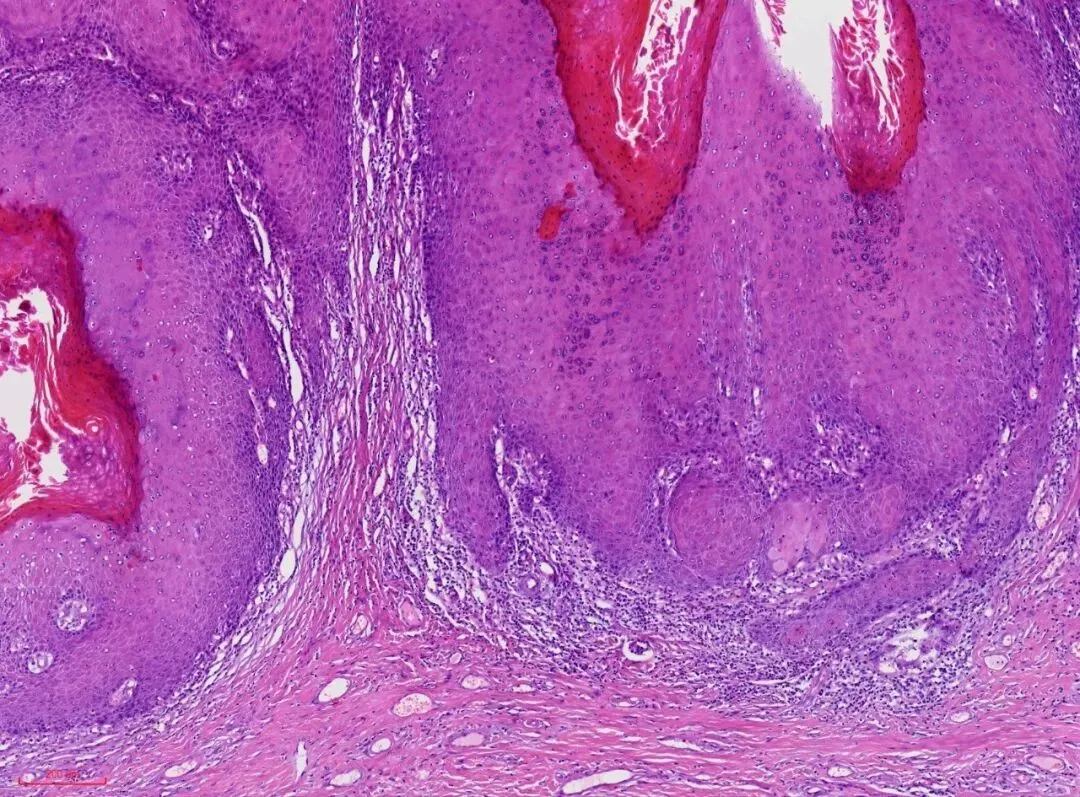

最近遇到一例外阴肿物,肿物比较大,直径约4cm,菜花状,表面有溃疡。显微镜下表现为鳞状上皮增生,呈宽带状延伸并形成乳头状生长模式,纤维血管轴心无或纤细,乳头表面有角化过度和角化不全。如下图

上皮脚粗大,呈圆形或棍棒样,推挤式浸润,如下图。

1.鳞状上皮增生,呈宽带状延伸并形成乳头状生长,纤维血管轴心无或纤细,乳头表面有角化过度和角化不全。棘层明显增厚,上皮角粗大,呈球状或棍棒样挤压推入上皮下间质。